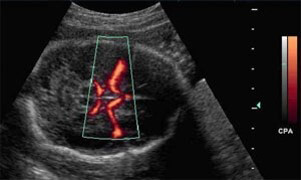

Examples of Images

Color Doppler is mostly used in fetal and hepatic ultrasound, where the primitive carotid and the hepatic vein are well visible.

In power Doppler mode, the energy of the echoes of the moving targets is color-coded and represented in each point of the image. Power Doppler is useful when examining superficial structures, like testis, renal grafts, thyroid, and subcutaneous lesions.